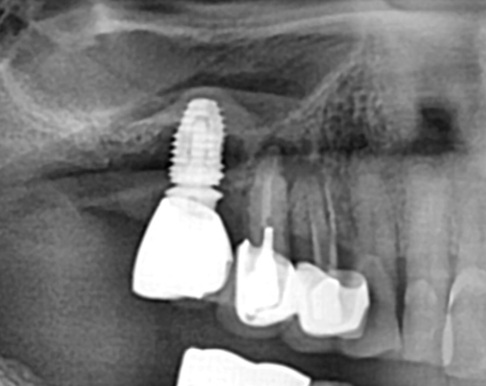

Before

임플란트도 각종 합병증이 생길 수 있고 본 케이스 처럼 잇몸 뼈가 70~80%이상 소실 되면

제거하고 다시 시술해야 할 수 있습니다.

잇몸 뼈가 많이 소실된 상태이므로 임플란트 재수술은 보통 더 어려울 수 밖에 없습니다.